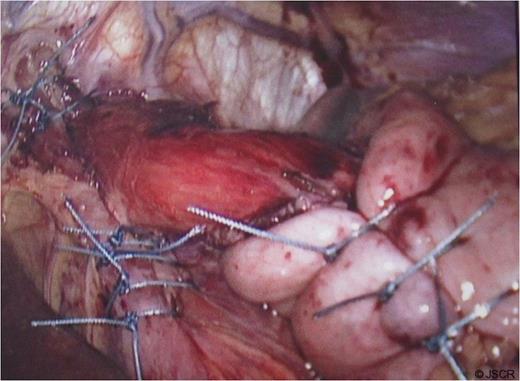

At operation, a large hiatal defect of 5cm and a moderate size sac was found (Fig 1) that was mobilised and adhesions divided to obtain 3cm of oesophageal length in the abdomen. Following division of the upper short gastric vessels, a posterior hiatal repair with seven interrupted ethibond stitches and a loose 360 degree full wrap with the fundus of the stomach with three interrupted ethibond stitches were performed. Wrap was further fixed to the diaphragm and right crus with another three ethibond stitches (Fig. 2).